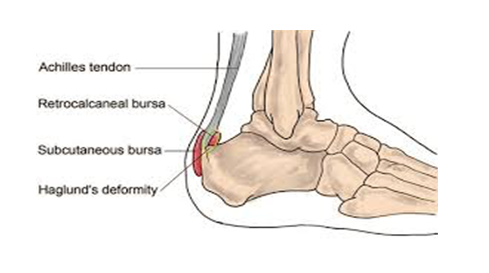

Haglund deformity:

A bony prominence on the back the heel with is often associated with a high angle of the heel bone. The prominent bony bump often irritates the bursa that sits over the bone.

Inflamed bursa:

A bursa is pocket of fluid which is found at the back of your heel. On occasions it can become inflamed and painful, but this rarely happens on its own and is usually associated with a bony problem too.